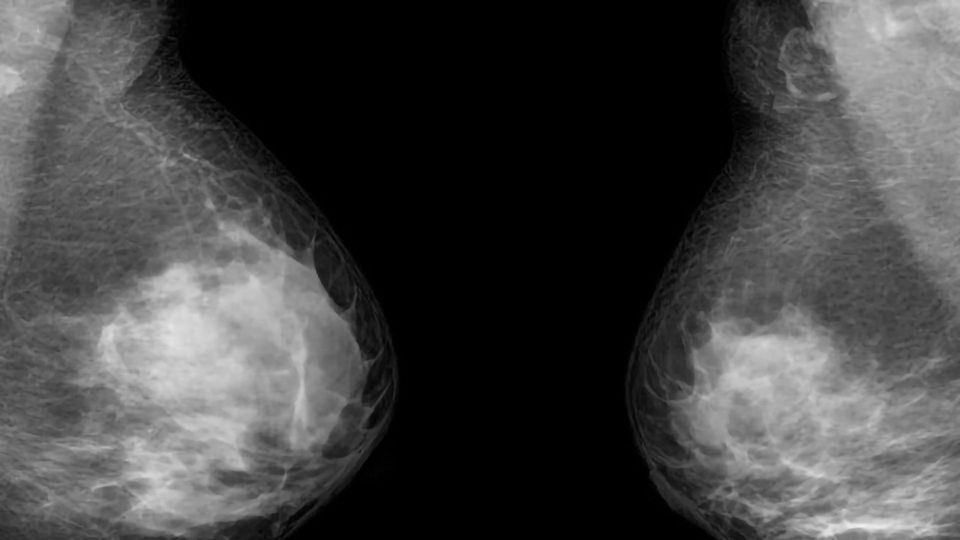

乳腺癌是女性癌症死亡的第二大原因。大约55000名女性被诊断为浸润性乳腺癌每年在英国,全球估计有200万例。

乳腺癌亚型的研究包括一个横截面,包括her2阳性、激素受体阳性,三阴性。收集血液样本每6个月到4年从每个病人,结果与影像学和临床结果。